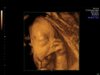

Jeg skal til gynokolgen imorgen. En time som jeg har hatt i noen mnd. Var litt fremogtilbake på om jeg bare skulle avbestille den, siden jeg nå har blitt gravid. Men legen sa at jeg bare kunne gå for en sjekk. Men sa til henne at jeg testet etter el, og da er jeg 4+1, når jeg skal til gynokolgen. Men hun sa at de bare går ut etter menstermin foreløpigt... Så da får jeg se hva gyn sier imorgen, så skal jeg bestille legetime etter 12 uke

Noen som har vært på ul, så tidlig? Så dere noe da?